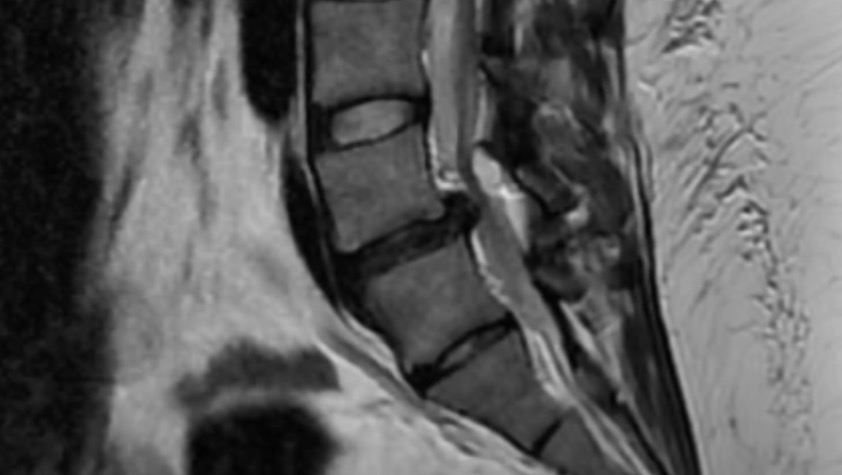

(MRI showing disk slippage, bone spurring & canal stenosis)

- A 7x8x10mm lesion (possibly a synovial cyst) that’s pressing into the spinal canal;

- Moderate spinal canal stenosis — narrowing of the spinal canal;

- Severe foraminal narrowing, especially on the right side — this is where the nerves exit the spine and it causes constant nerve pain;

- Disc protrusion that compresses the thecal sac (the protective sheath around the spinal cord); and